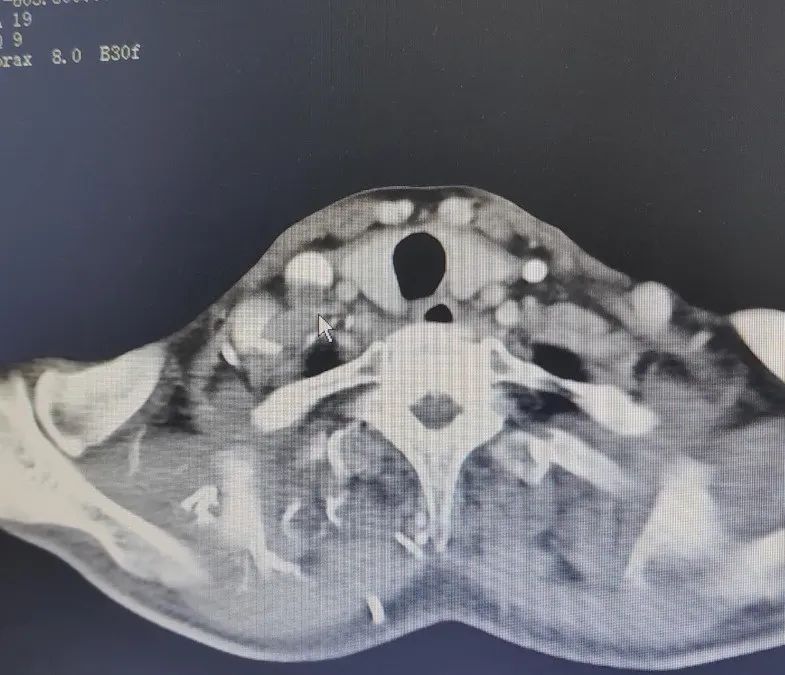

2023年11月

碘粒子植入術(shù)前

影像檢查

2024年6月

碘粒子植入術(shù)后

7個月復查結(jié)果